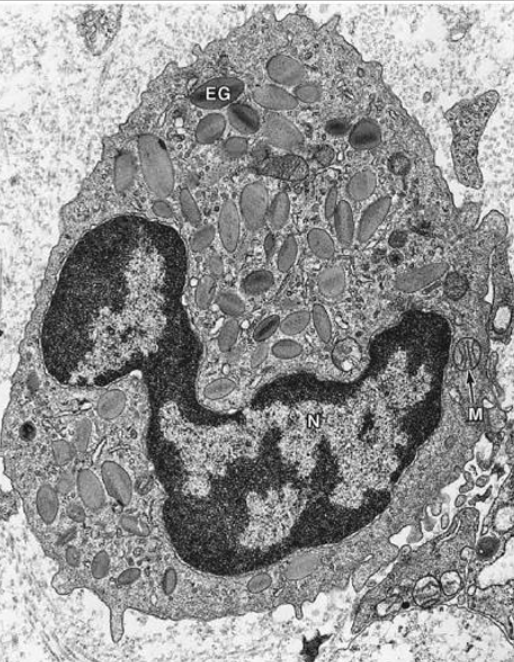

Monocito